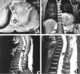

Paraplegia is an impairment in motor or sensory function of the lower extremities. The word comes from Ionic Greek (παραπληγίη) "half-stricken". [Source: Wikipedia ]